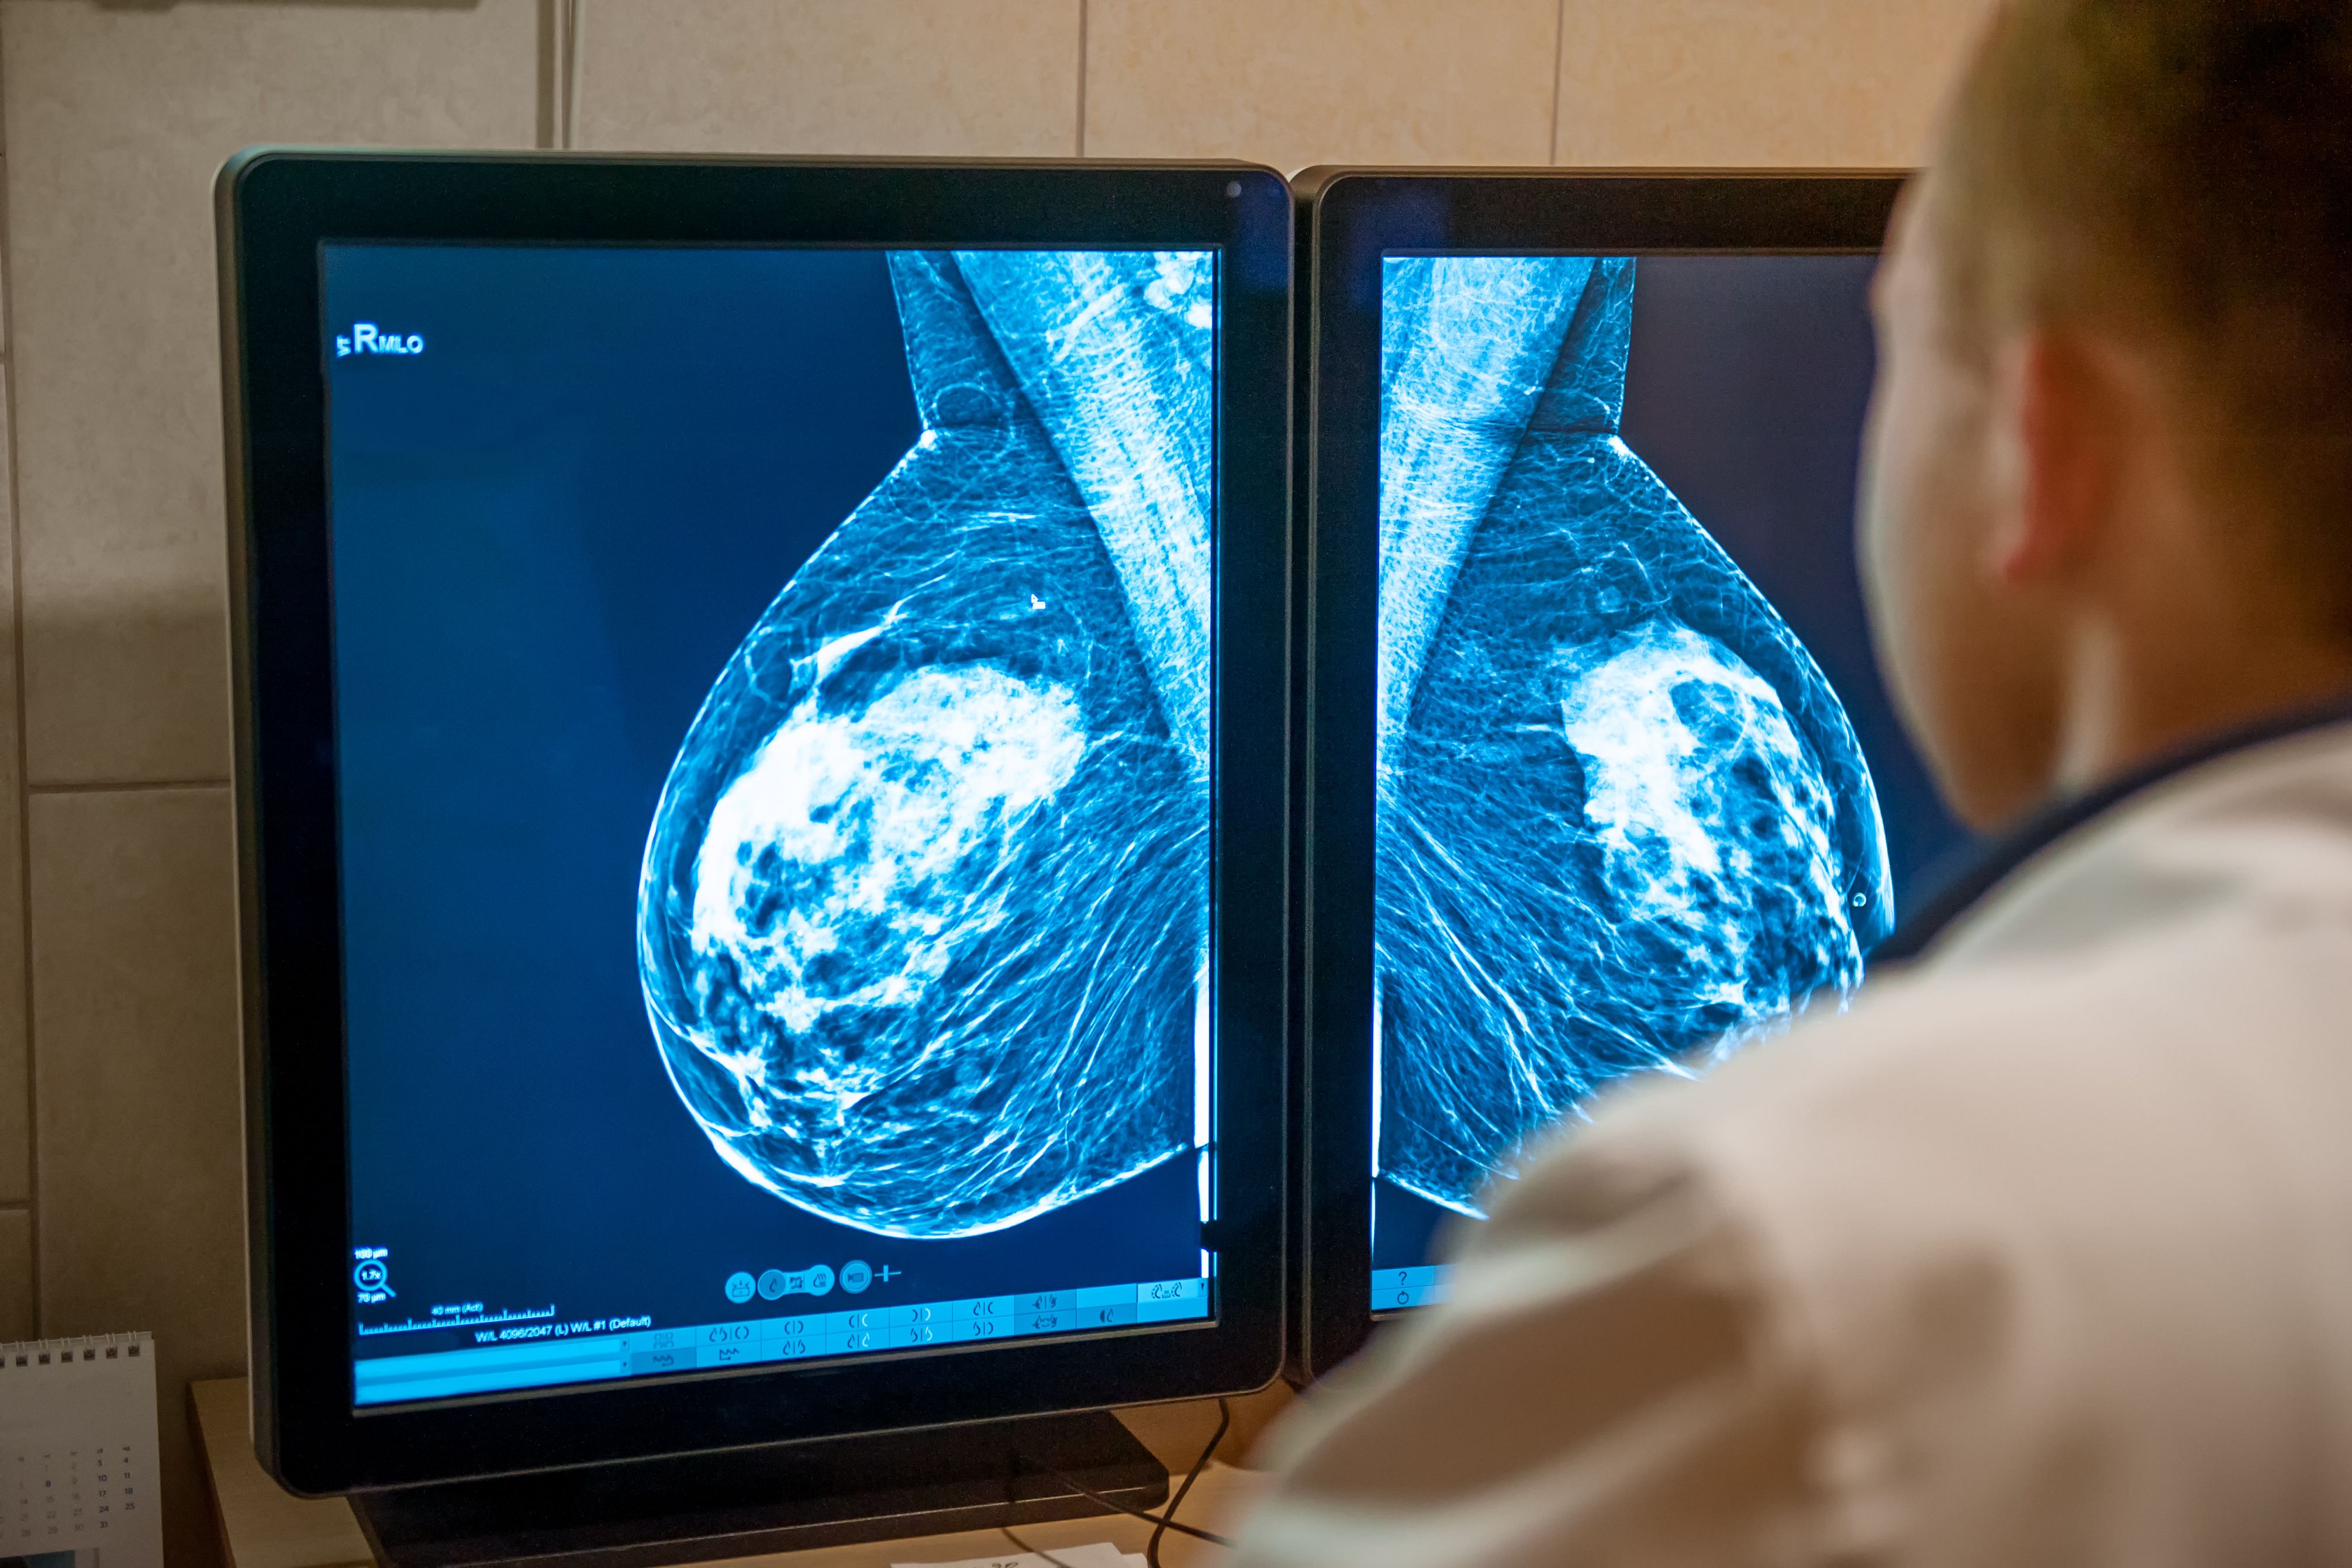

Octubre es el Mes de Concientización sobre el Cáncer de Mama y, aunque es importante que los oncólogos tengan una comprensión integral del impacto de la afección en todo el cuerpo, los dermatólogos desempeñan un papel importante en un plan de atención multidisciplinario. Las afecciones de la piel pueden estar relacionadas con la aparición, el desarrollo y el tratamiento del cáncer de mama. “Los dermatólogos pueden ser los primeros en establecer el diagnóstico de cáncer de mama, como un subconjunto de pacientes que presentan por primera vez una extensión directa del tumor primario o con metástasis cutánea”, según Milam et al.1

- Los dermatólogos pueden ser los primeros en establecer un diagnóstico de cáncer de mama y desempeñar una parte integral de un plan de atención multidisciplinario para los pacientes.

- Una variedad de enfermedades de la piel pueden surgir como resultado del tratamiento quirúrgico y de radiación del cáncer de mama.

El tratamiento quirúrgico puede poner sobre la mesa una variedad de afecciones de la piel, incluido linfedema posoperatorio, infecciones de tejidos blandos, seromas, pioderma gangrenoso y trastornos cicatriciales. La radioterapia aplicada a los senos a menudo puede provocar cambios en la piel, desde lesiones cutáneas leves hasta úlceras desfigurantes, fibrosis y necrosis. Otras afecciones raras pueden incluir angiosarcoma, morfea inducida por radiación, liquen plano y paniculitis pseudoesclerótica después de la irradiación.

Beth McLellan, MD, profesora de dermatología en la Facultad de Medicina Albert Einstein en el Bronx, Nueva York, tiene un interés especial en la oncología cutánea de apoyo. Fue presentada durante una sesión titulada «Más allá del sostén: lo que los dermatólogos deben saber sobre las enfermedades mamarias» a principios de este año en la reunión anual de la Academia Estadounidense de Dermatología en Nueva Orleans, Luisiana. Su atención se centró en los efectos adversos de los tratamientos contra el cáncer de mama. Presentó 4 casos y muchas perlas a sus compañeros de dermatología.2

Caso 1: Mujer de 31 años con carcinoma intraductal invasivo.

El tratamiento del cáncer para esta paciente incluyó quimioterapia neoadyuvante seguida de mastectomía bilateral con reconstrucción. Inicié radioterapia adyuvante con 50.4llegando a la pared torácica y a los ganglios linfáticos. La radiación ha sido una herramienta eficaz para tratar el cáncer durante más de 100 años y aproximadamente el 90% de los pacientes desarrollarán dermatitis por radiación.3

Caso 2: Mujer de 61 años con antecedentes de carcinoma ductal invasivo y carcinoma de células escamosas.

Esta paciente se sometió a una mastectomía derecha con preservación de la piel con reconstrucción con implantes y disección axilar junto con quimioterapia, radioterapia y anastrozol. Ha visitado a su dermatólogo y tiene antecedentes de 7 días de erupción por radiación con picazón que se extiende hasta el cuello. Su diagnóstico fue erupción eosinófila, polimorfa y pruriginosa asociada a la radioterapia, más común después del cáncer de cuello uterino y de mama. Puede simular penfigoide ampolloso y dermatitis herpetiforme. A menudo ocurre fuera de las áreas irradiadas y el riesgo parece depender de la dosis (media 30 Gy).

Caso 3: Mujer de 62 años con carcinoma ductal infiltrante estadio IIA, ganglios linfáticos negativos.

Fue tratada con mastectomía parcial de mama izquierda, radioterapia y quimioterapia (AC-T; clorhidrato de doxorrubicina). [Adriamycin]Ciclofosfamida y paclitaxel [Taxol]). Tres semanas después de la radiación, la paciente experimentó enrojecimiento e hinchazón en el seno izquierdo y se sometió a tres ciclos de cefalexina (Keflex) sin mejoría. Múltiples biopsias de piel mostraron cambios radiológicos y fibrosis. El diagnóstico fue morfea después de la irradiación y notó mejoría con pentoxifilina y vitamina E.

Caso 4: Mujer de 45 años con antecedente de cáncer de mama izquierda.

Se sometió a quimioterapia neoadyuvante seguida de mastectomía bilateral con preservación de la piel con colocación de expansor de tejido, radiación adyuvante y tamoxifeno. Seis meses después de la cirugía, fue remitida por un exantema asintomático en la mama lateral derecha. Previamente, el paciente no había respondido a emolientes ni a trimetoprim-sulfametoxazol. Se le administró un ungüento de fluocinonida al 0,05%. La erupción mejoró pero reapareció, lo que requirió una biopsia por afeitado. Una biopsia por afeitado condujo al diagnóstico de dermatitis numérica en la mama reconstruida.